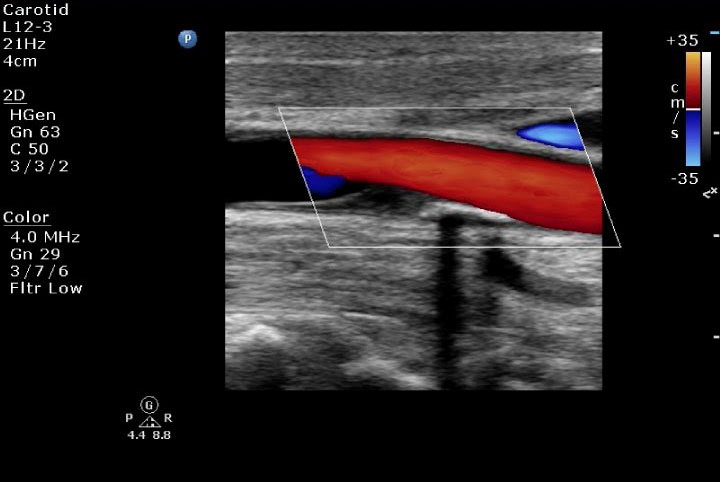

1. Doppler Ultrason

2. Duplex Ultrason